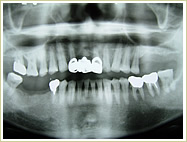

●歯を数本失った場合

60歳 男性 インプラント埋入数:6本 画像拡大

治療前 治療後

治療前